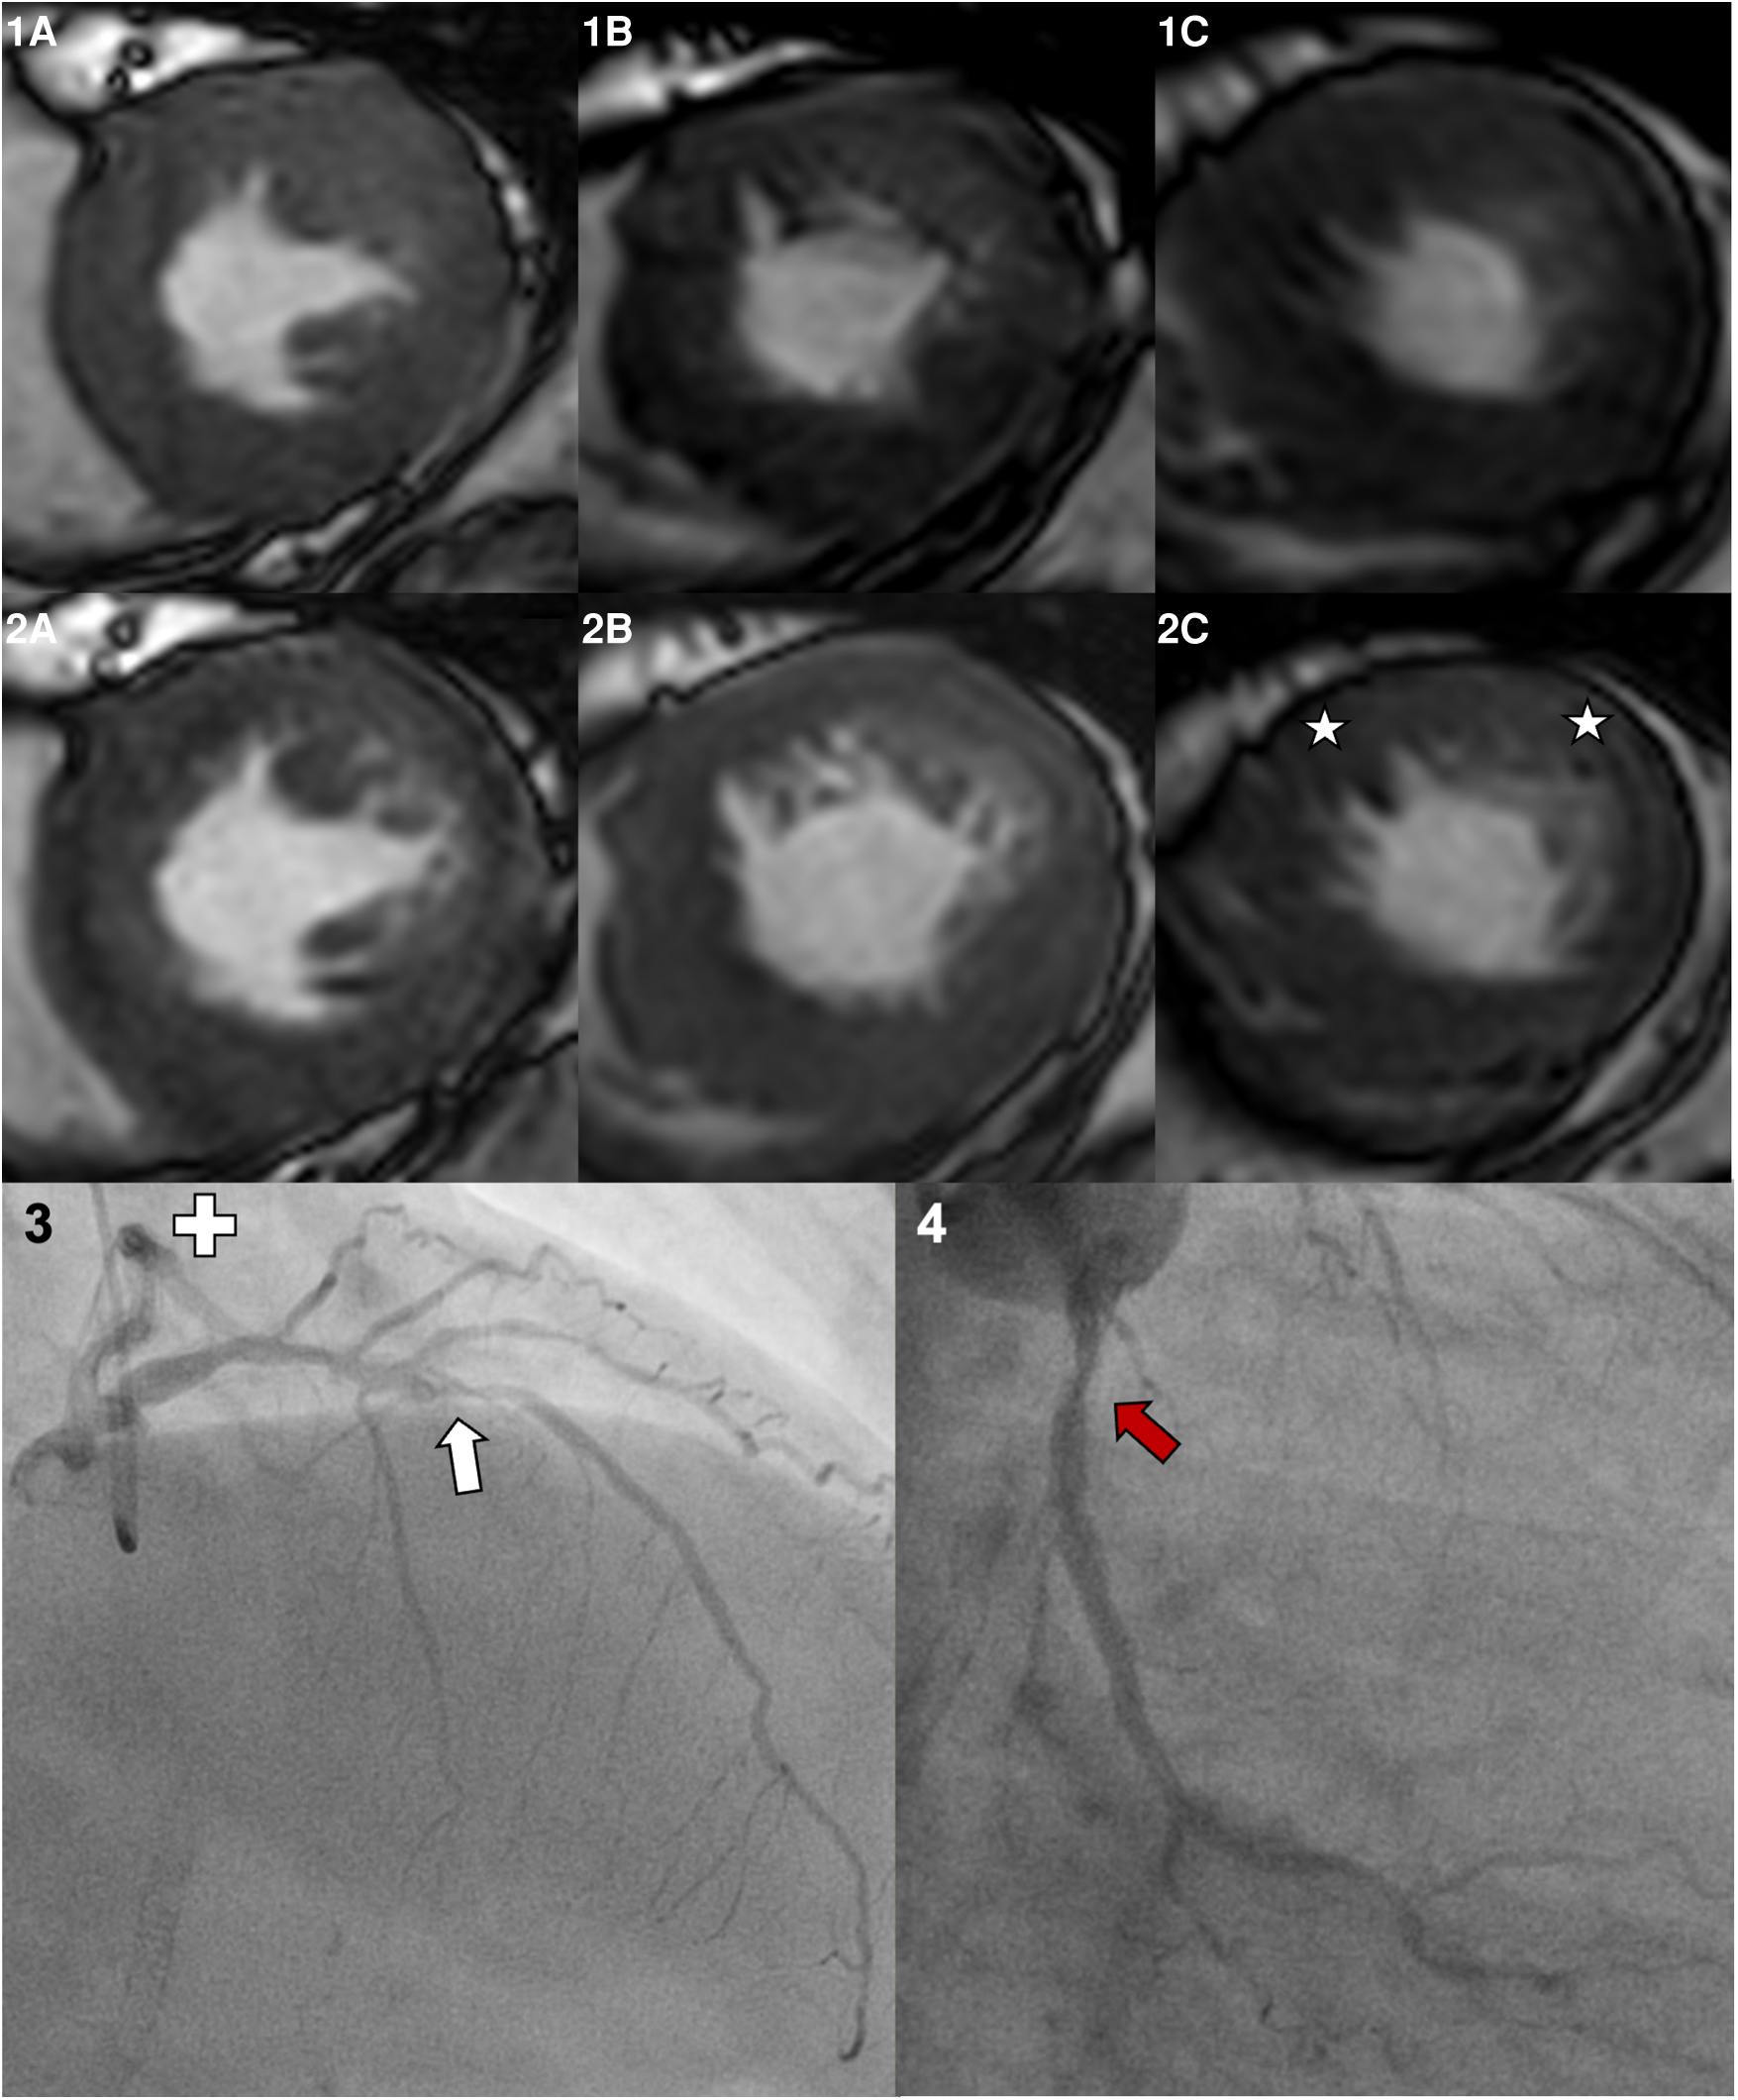

A 55-year-old female patient undergoing dobutamine stress CMR prior to kidney transplantation. Her past medical history included a percutaneous coronary intervention of the right coronary artery with stent implantation but no myocardial infarctions. The LV-EF at rest was good (57%), and the target heart rate of 142/min (86.1% of HFmax) was reached applying 40 µg/kg/min dobutamine and 0.75 mg atropine. Panel 1 shows the basal (A), midventricular (B), and apical (C) short axis slices at rest. Panel 2 shows images during peak stress, a globally reduced response to peak stress with emphasis on the anterior and lateral wall, and the apical slice (stars) is visible. Consecutive invasive coronary angiography showed a severe stenosis in the left anterior descendent artery (white arrow). The left circumflex artery (Panel 4, separate ostium) shows a moderate coronary stenosis (red arrow). The right coronary artery was inconspicuous beside the previous stent implantation.